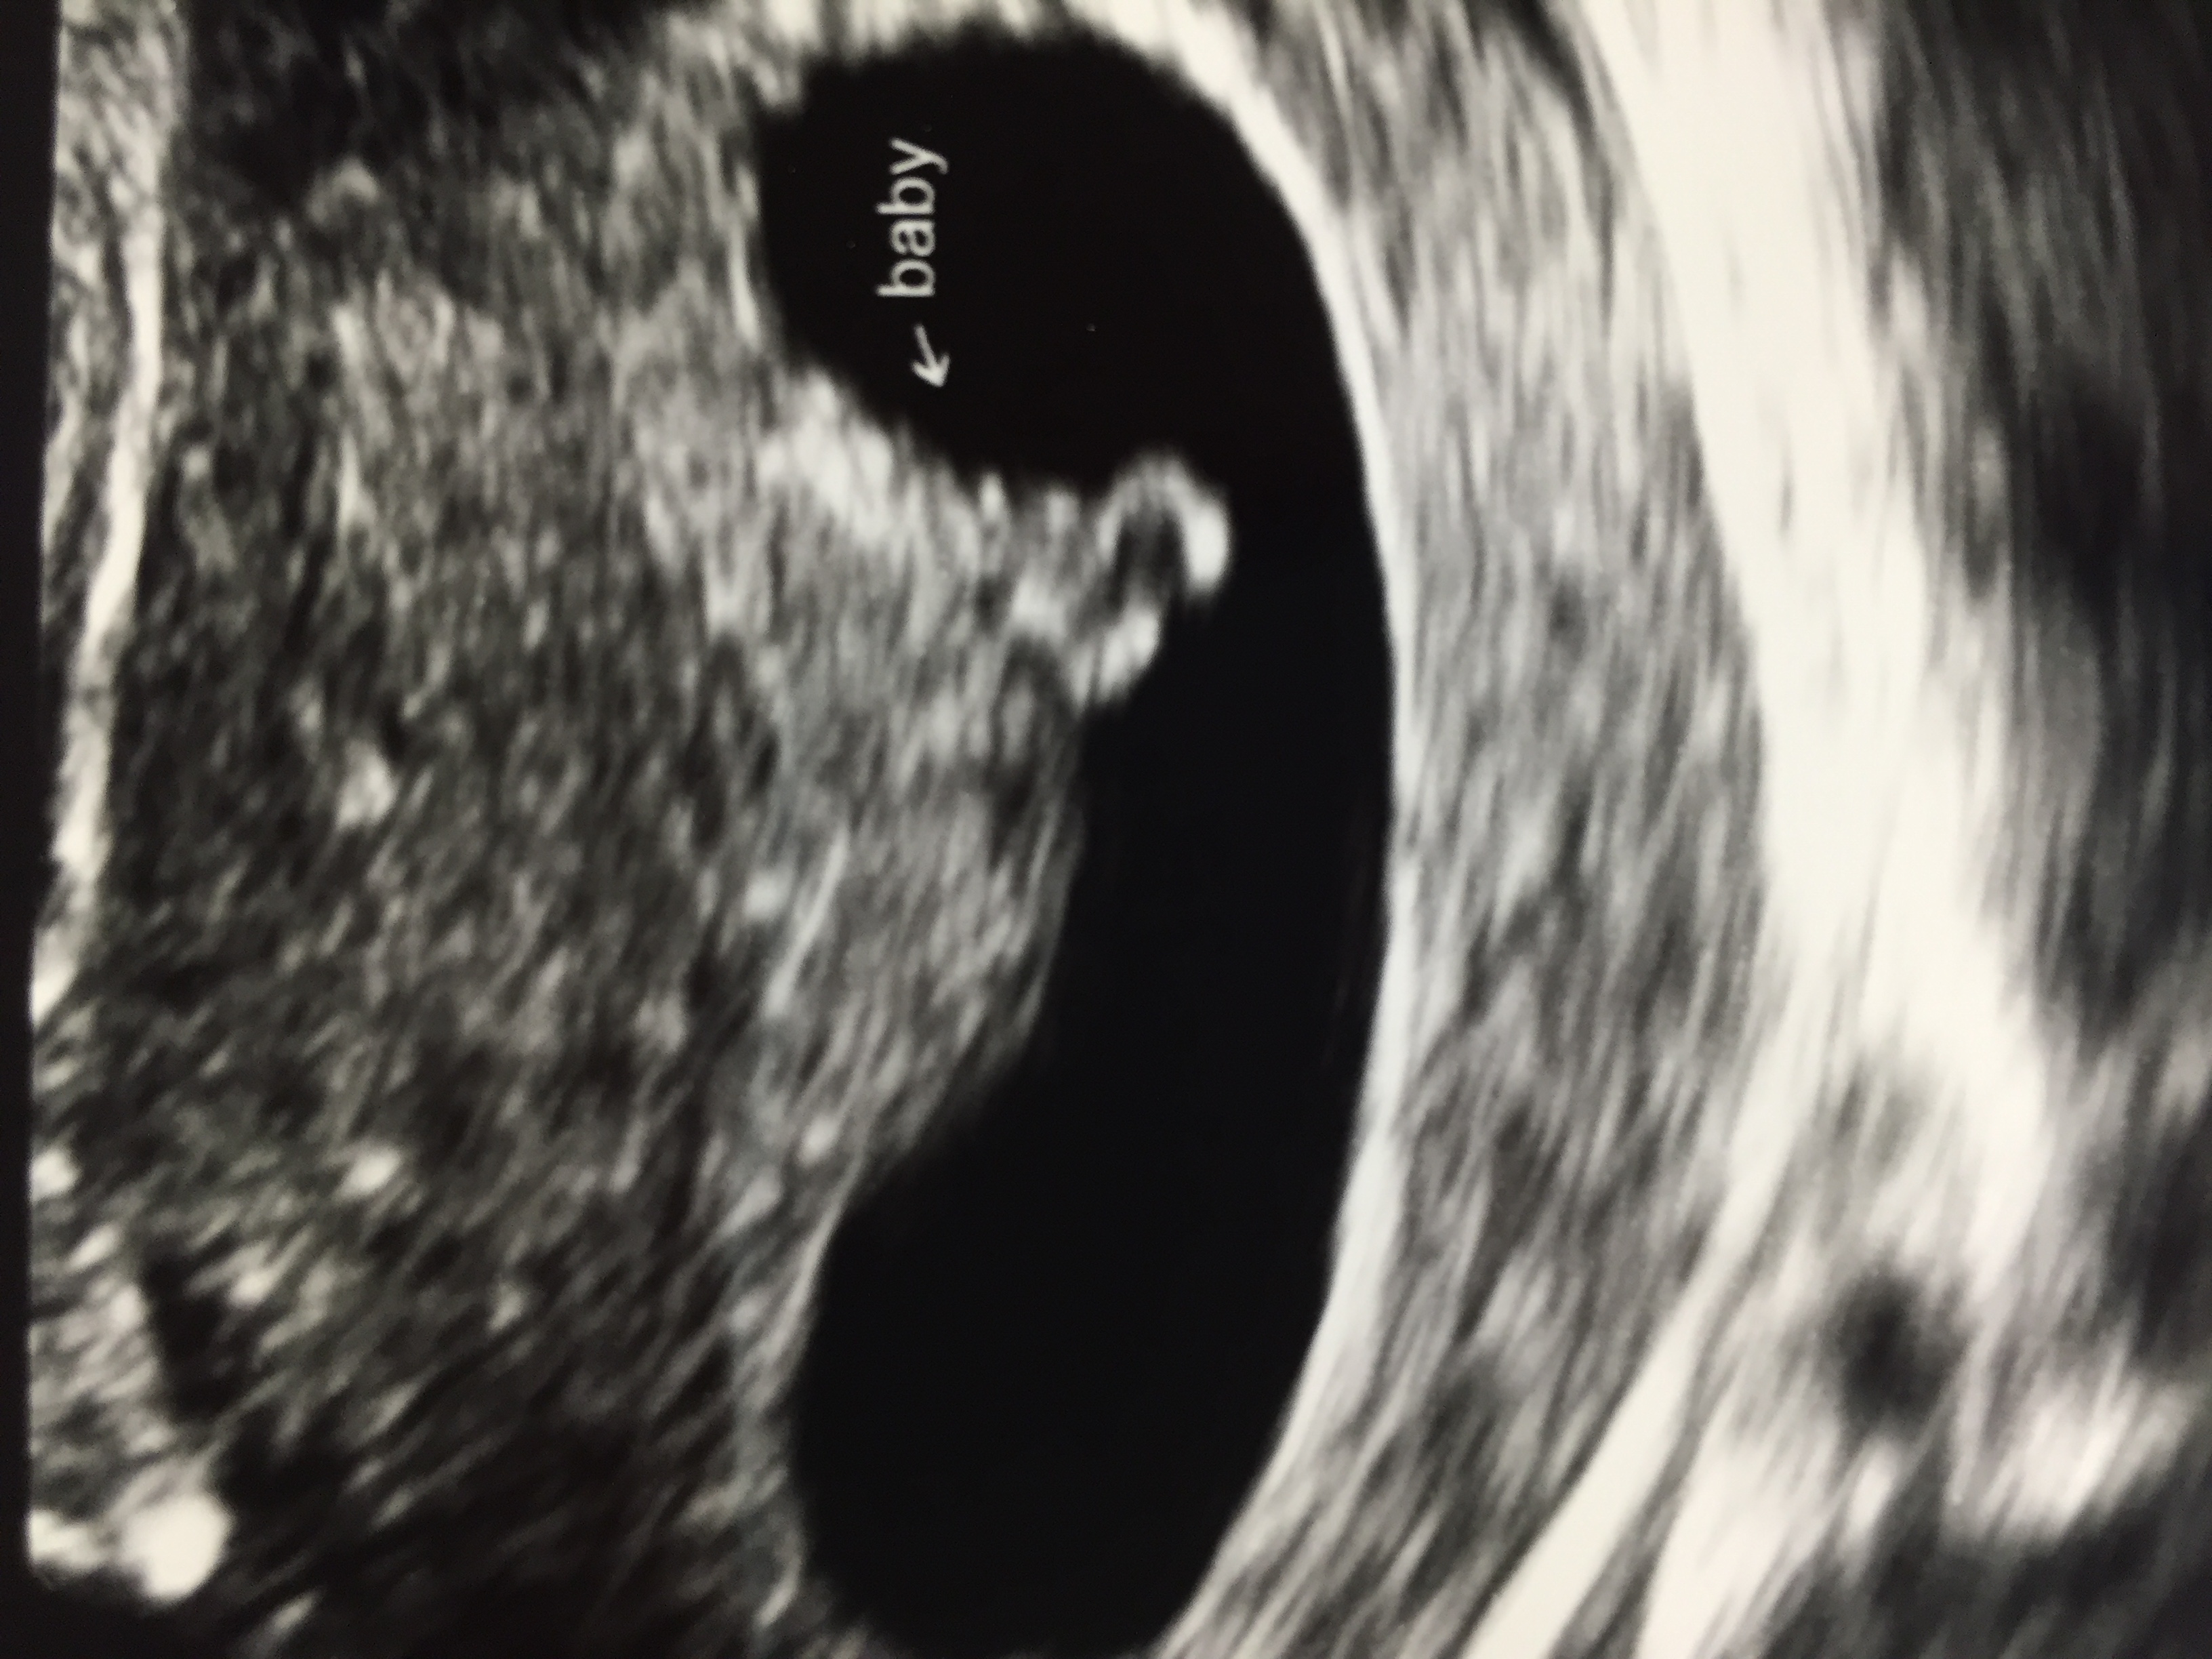

@mrsshmitty I just had my second u/s because I am considered high risk, one last Wednesday, one today. I'm 7 weeks today and will have a 3rd u/s in two weeks. My doc usually won't do them until at least 10 weeks. I'd rather not have so many, but after a late, 19 week, miscarriage in June... Here is my tadpole

Here is my tadpole